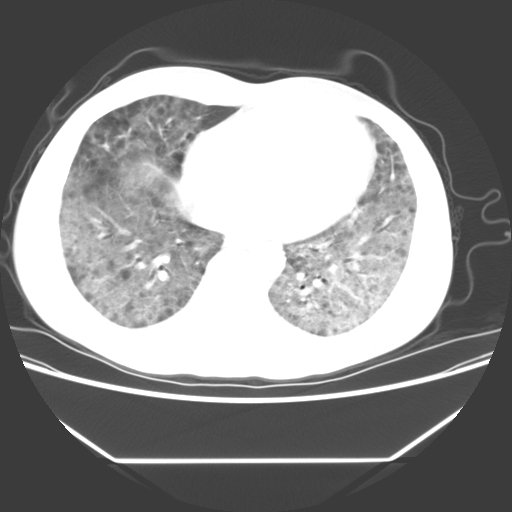

病人55岁,咳嗽,胸闷

忘了传病史了,病人55岁,咳嗽,胸闷

两肺部呈“毛玻璃”状改变,原因待查考虑感染性病变

病人是否发烧,两肺“磨玻璃”影,其间见空气支气管征和碎路石征。考虑肺泡蛋白沉着症。

两肺广泛对称磨玻璃样影,密度不均,考虑机遇性肺部感染。

双肺弥漫磨玻璃样病变,病史很重要。有感冒或发烧史,甲流不除外。无发烧可考虑肺泡蛋白沉积,但肺泡蛋白沉积边缘往往较清晰,与正常肺组织分界清晰

两肺弥漫间质性病变,考虑肺泡蛋白沉着症。建议进一步检查。